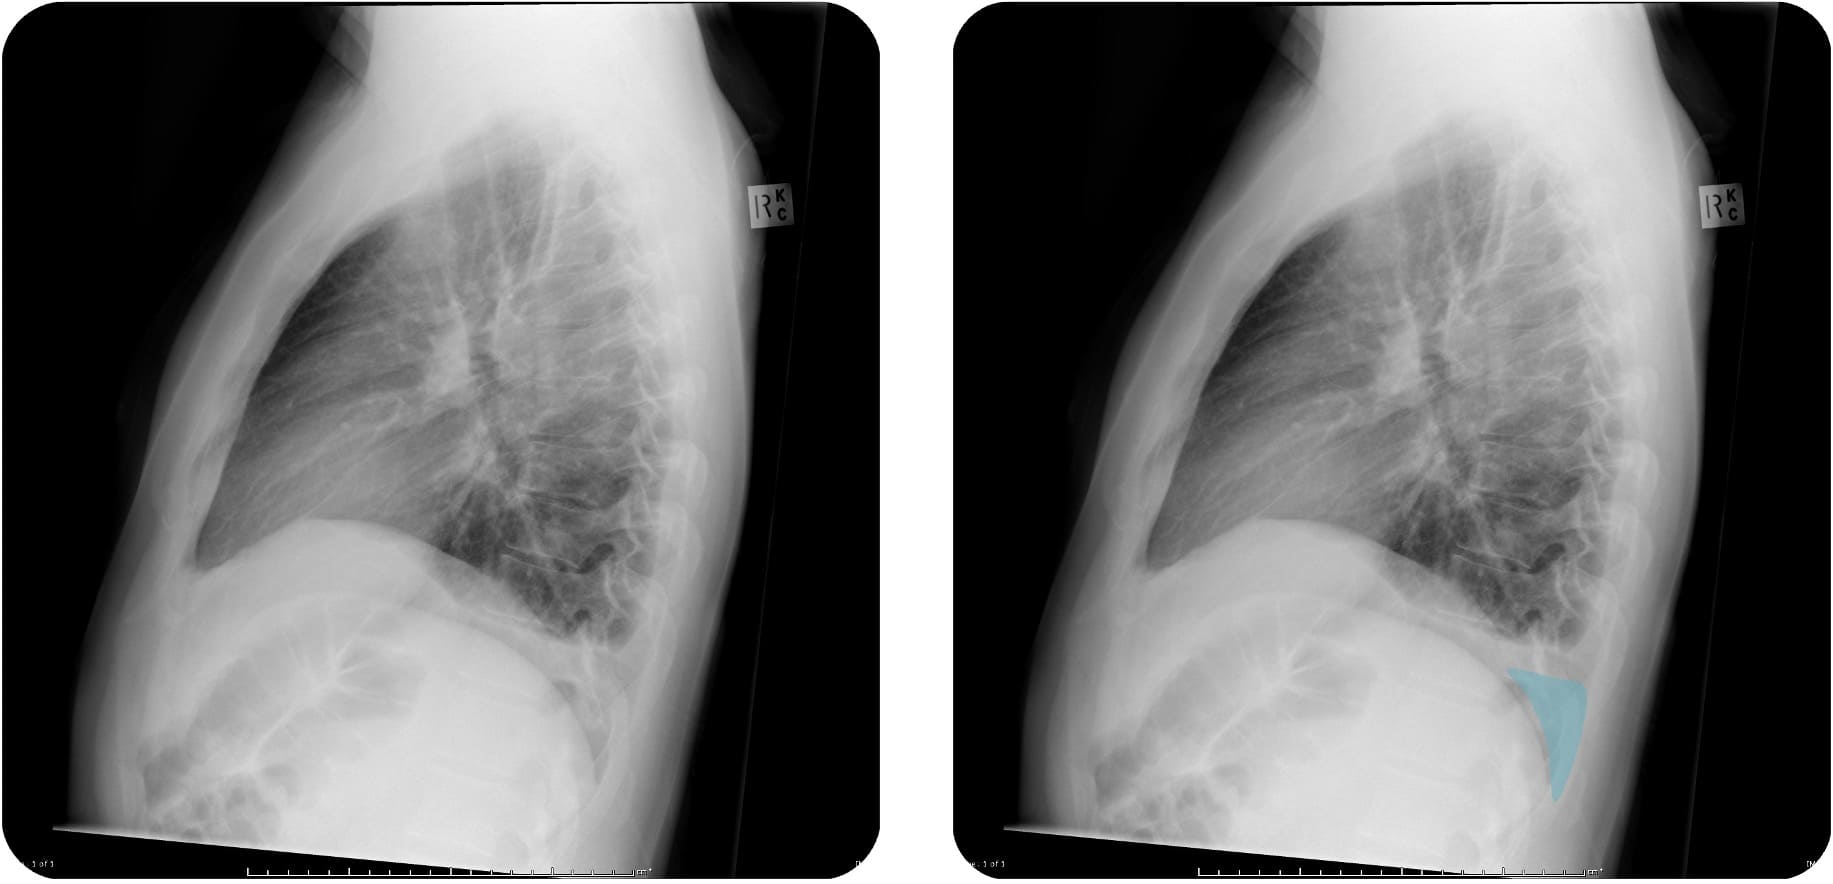

Zur Beurteilung eines Pleuraergusses wird eine Aufnahme im Stehen in 2 Ebenen angefertigt. Der Erguss sammelt sich in Richtung der Schwerkraft am tiefsten Punkt des Thorax

Da der hintere Teil des Recessus costodiaphragmaticus tiefer liegt als der vordere, lassen sich kleine Ergüsse am besten in der Seitaufnahme

Case courtesy of Craig Hacking, Radiopaedia.org, rID: 80388